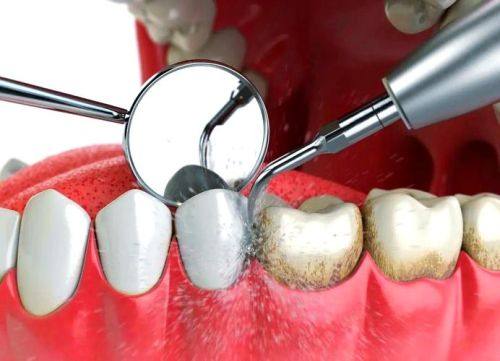

2. 口腔预防保健:为患者提供特色的口腔健康指导,帮助患者树立正确的口腔保健意识,预防口腔疾病的发生。

1. 洗牙:100 - 300元